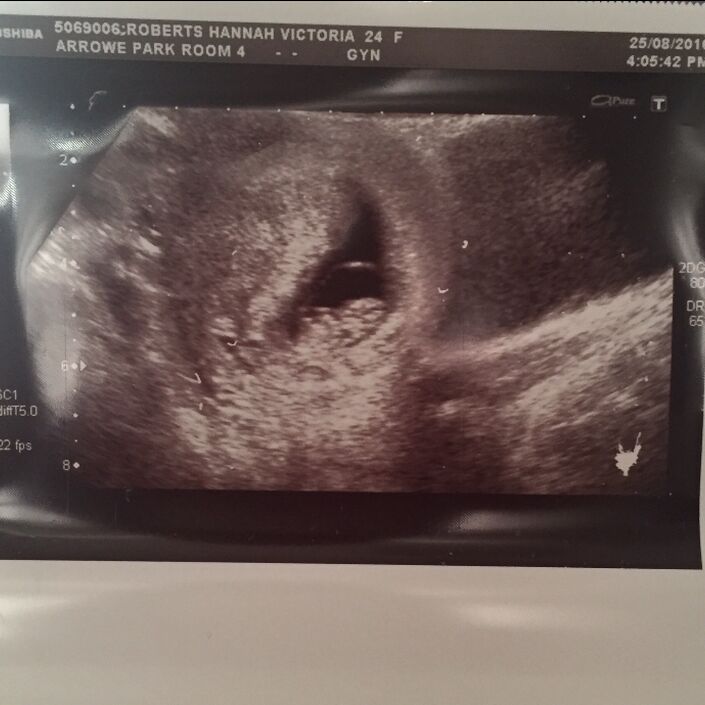

We were quite shocked when we found out we were going to have twins. Although I was a little big for 12 weeks, it was still a surprise when the sonographer said, "There’s baby number 1… and there’s baby number 2…" However, once we were over the initial shock, we were really excited and got busy researching what to expect and what to buy.